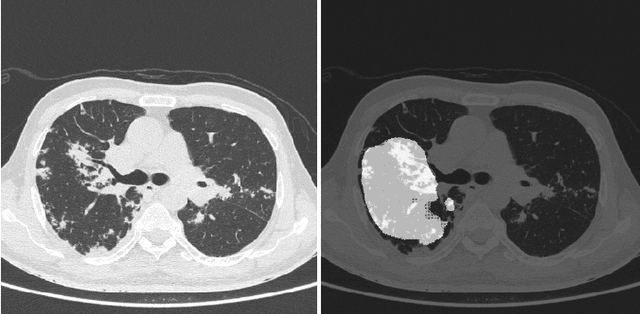

Abstract:COVID-19 is an infectious disease that causes respiratory problems similar to those caused by SARS-CoV (2003). Currently, swab samples are being used for its diagnosis. The most common testing method used is the RT-PCR method, which has high specificity but variable sensitivity. AI-based detection has the capability to overcome this drawback. In this paper, we propose a prospective method wherein we use chest CT scans to diagnose the patients for COVID-19 pneumonia. We use a set of open-source images, available as individual CT slices, and full CT scans from a private Indian Hospital to train our model. We build a 2D segmentation model using the U-Net architecture, which gives the output by marking out the region of infection. Our model achieves a sensitivity of 96.428% (95% CI: 88%-100%) and a specificity of 88.39% (95% CI: 82%-94%). Additionally, we derive a logic for converting our slice-level predictions to scan-level, which helps us reduce the false positives.